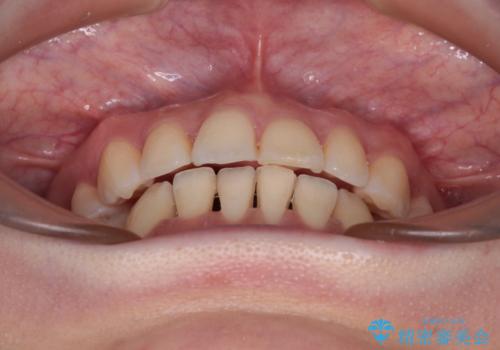

- 口元の閉じにくさを気にして来院された患者様です。

上下ともに歯列が前方に突出していたため、上下左右の第一小臼歯4本を抜去し、ワイヤー装置による矯正治療を行うこととしました。

舌の突出癖がなかなか改善されず、上下前歯の接触がやや甘い状態での仕上がりとなりました。

接触が甘い場合、上顎前歯の叢生が後戻りを起こしやすくなるため、治療終了後の保定期間でも舌のトレーニングを継続するように指示しています。